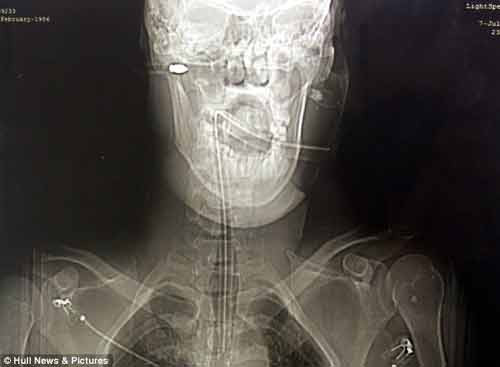

| Ảnh chụp X-quang mũi tên nỏ xuyên qua đầu của Rolanda Gedminas. |

Nạn nhân là anh Rolanda Gedminas, 27 tuổi. Anh có thể đã tử vong nếu mũi tên bắn vào đầu chỉ lệch vào sâu hơn hoặc cao hơn một vài mm. Gedminas gặp phải tai nạn kinh hoàng này trong một vụ ẩu đả với nhiều người trong một công viên ở Grimsby.

Khi Gedminas đã được đưa tới bệnh viện trong tình trạng bất tỉnh với mũi tên nỏ vẫn cắm trên đầu. Khi phẫu thuật loại bỏ mũi tên, các bác sĩ phát hiện nó đã đâm trúng vào một tuyến nước bọt của anh. Nếu mũi tên này đâm sâu hoặc lệch vào khoảng 1mm nữa thì nó có thể đã làm đứt động mạch hoặc cuống não của nạn nhân, gây tử vong lập tức.